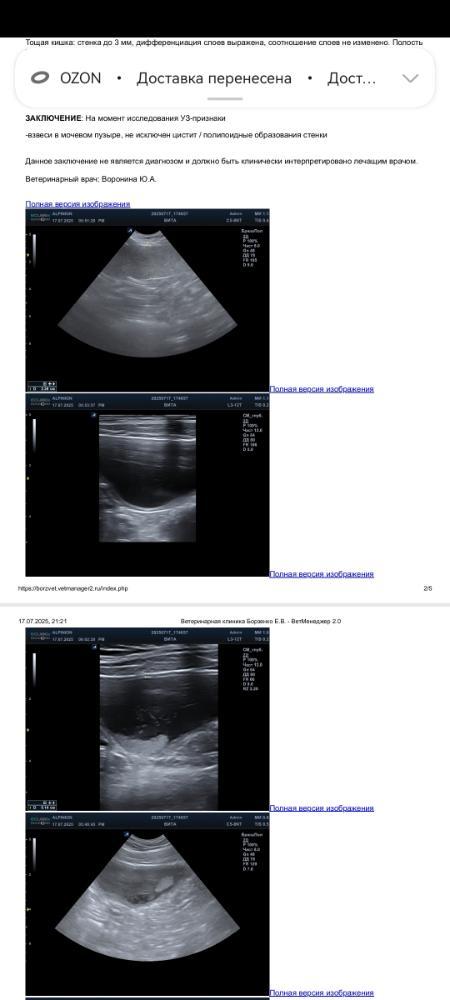

Отчет по узи Виты

Screenshot_20250717_212519_com.huawei_docs.jpg.93e5ac74a0ed2fbaf03cccd0e837a944.jpg

Screenshot_20250717_212527_com.huawei_docs.jpg.04096fcbcb65538b2ab66643a3ddf317.jpg

Screenshot_20250717_212536_com.huawei_docs.jpg.522b5d1efe21e0a7e32ab80ac4e85473.jpg

Screenshot_20250717_212545_com.huawei_docs.jpg.a7e95bbe4921de97e29617162daaccc8.jpg

IMG_20250717_200923.jpg.90f96118e1606537cfcc19872f954792.jpg

Минус пока пойдет в неш общий котел, если Оксанаможет его закрыть, то потом просто это напишу и скорректирую.

Узи Вита - 2 500 рублей

Итого: минус 37 950.46 руб.